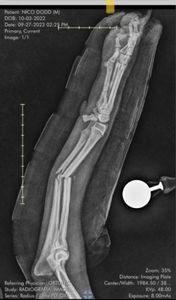

Oi amigos, me Chamo Barbara e sou mamãe do Nico, um vira-lata meio poodle, que já nasceu sofrendo. Vindo de um canil, já com 45 dias estava com pavovirose, e ele seria sacrificado. Foi amor à primeira vista e depois de um longo e caro tratamento contra a pavovirose, filnamente Nico conheceu a felicidade e é super carinhoso, meigo e amigo de crianças. Ocorre que semana passada, ao pular de um móvel, Nico sofreu uma grave fratura na pata dianteira. Tentamos imobilizar em casa e dar remédio pra dor, pois o valor da cirurgia seria muito alto. Infelizmente a fratura não melhorou e encontrei a clínica especializada em ortopedia veterinário ORTOTEC, que foram maravilhosos com ele, entretanto como a fratura estava muito feia e infeccionada, seria urgente fazer a cirurgia no mesmo dia, dia 27/09, pois ele poderia perder a pata ou até mesmo falecer. O total da cirurgia junto com a placa deu o valor de R$ 8.865,00. Desesperada e sem o valor, eu assinei duas notas provisórias e preciso pagar pra a clínica que está cuidando tão bem dele. Por favor, peço ajuda para que meu cachorrinho que precisa de cirurgia para poder ter qualidade de vida, pois ele é tão puro e já sofreu muito. Nico nasceu para ser feliz e será, eu acredito.

Pagamento do valor da Cirugia, estadia no centro de reabilitação da clínica por 3 dias, pagamento da prótese de titânio, fisioterapia e radiografia. Totalizando R$ 8865,00